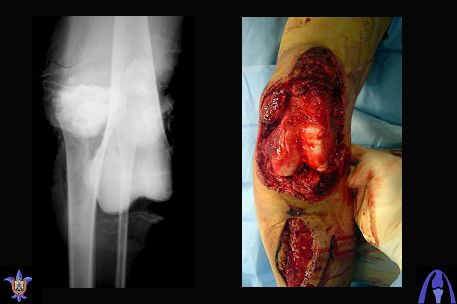

Re: open dislocation of the knee joint

На ренгенограмме хорошая аппозиция костей коленного сустава, но надколенник находится подозрительно высоко, поэтому необходимо убедиться в отсутствии повреждения связки надколенника.

Снимки прошлых публикации из моего Power point